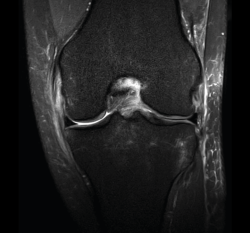

1.1. Meniscos

Se identifican como estructuras hipointensas en todas las secuencias, con asta anterior y posterior de morfología triangular.

La RM es la técnica de elección en el diagnóstico de la patología meniscal(17)(Figuras 30, 31, 32, 33, 34 y 35).

Figura 32. Corte de secuencia coronal T2 Fat-Sat de resonancia magnética de rodilla: rotura de menisco interno horizontal.